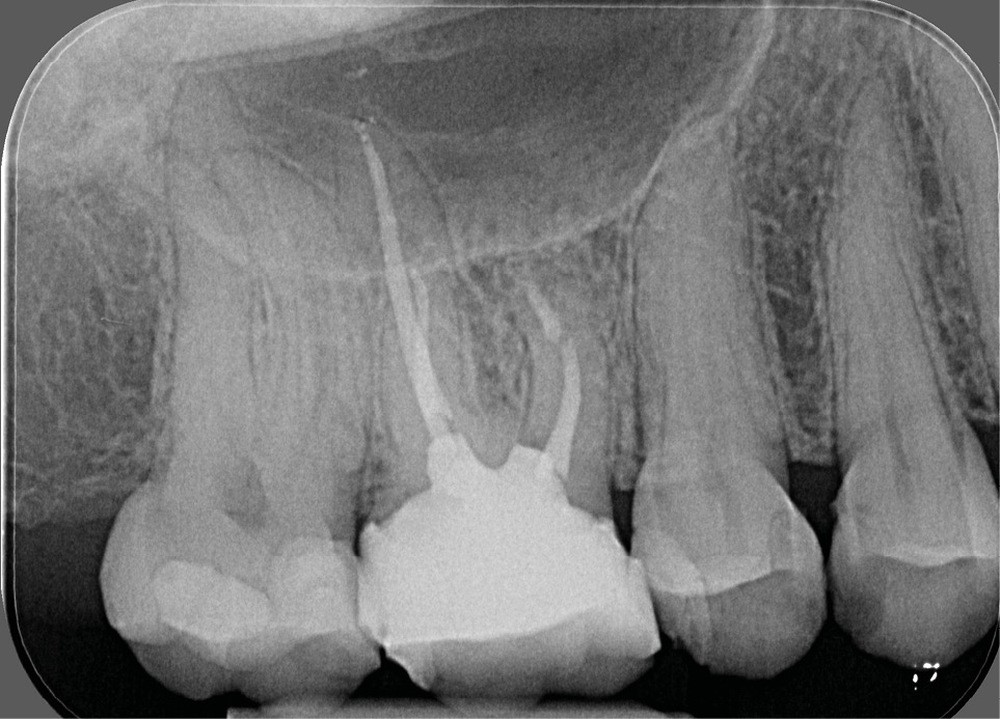

- une pathologie péri-radiculaire ne guérit pas à la suite d’un (re)traitement (fig. 1a-b) ;